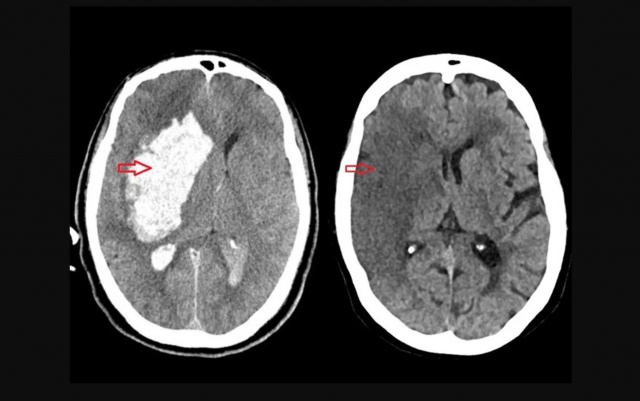

O AVC pode ser isquêmico (quando há entupimento de vasos sanguíneos, responsável por 85% dos casos) ou hemorrágico (causado por rompimento de vasos). O primeiro é mais comum; o segundo, mais grave.